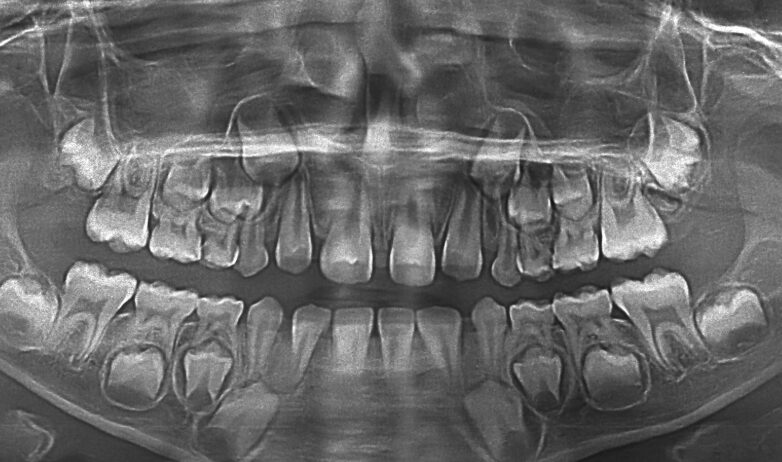

歯のスタートはいつ?|胎生6〜7週ごろに“歯のもと”ができ始めます

乳歯(子どもの歯)の準備は、妊娠初期のかなり早い時期から始まります。

目には見えませんが、上あご・下あごの骨の中に、将来の歯の“芽”となる組織が作られていきます。

- 胎生6〜7週ごろから乳歯の準備がスタート

- 上あご・下あごにそれぞれ10個ずつ“歯のもと”ができる

- 骨の中で少しずつ歯の形が整っていく

硬くなる工程「石灰化」|生後8か月ごろから乳歯が生えてきます

歯の形が整った後は、少しずつ硬くなっていく工程(石灰化)が進みます。

石灰化が進むと、歯は強度を増し、やがて歯ぐきの上に現れます。

乳歯が生える目安

- 最初に生えやすいのは下の前歯

- 目安は生後8か月ごろ(個人差があります)

- 乳歯は2〜3年ほどかけて生えそろいます

実は永久歯も早い|“妊娠中〜幼少期”の生活が将来の歯に影響します

永久歯はもっと先の話…と思われがちですが、永久歯の準備も早い時期から進みます。